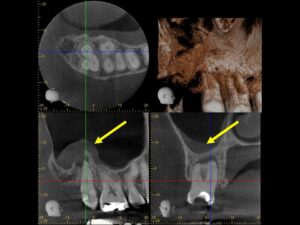

再根管治療後レントゲン。多少の違和感はあったものの、根管内部がきれいになり、排膿を認めないことから根管充填(薬を詰めること)を行った。根尖部までしっかりと薬が詰まっているのが分かる。歯根の内部がきれいな状態であれば、歯科医にはそれ以上出来ることはない。悪戯に弄り過ぎてはいけない。